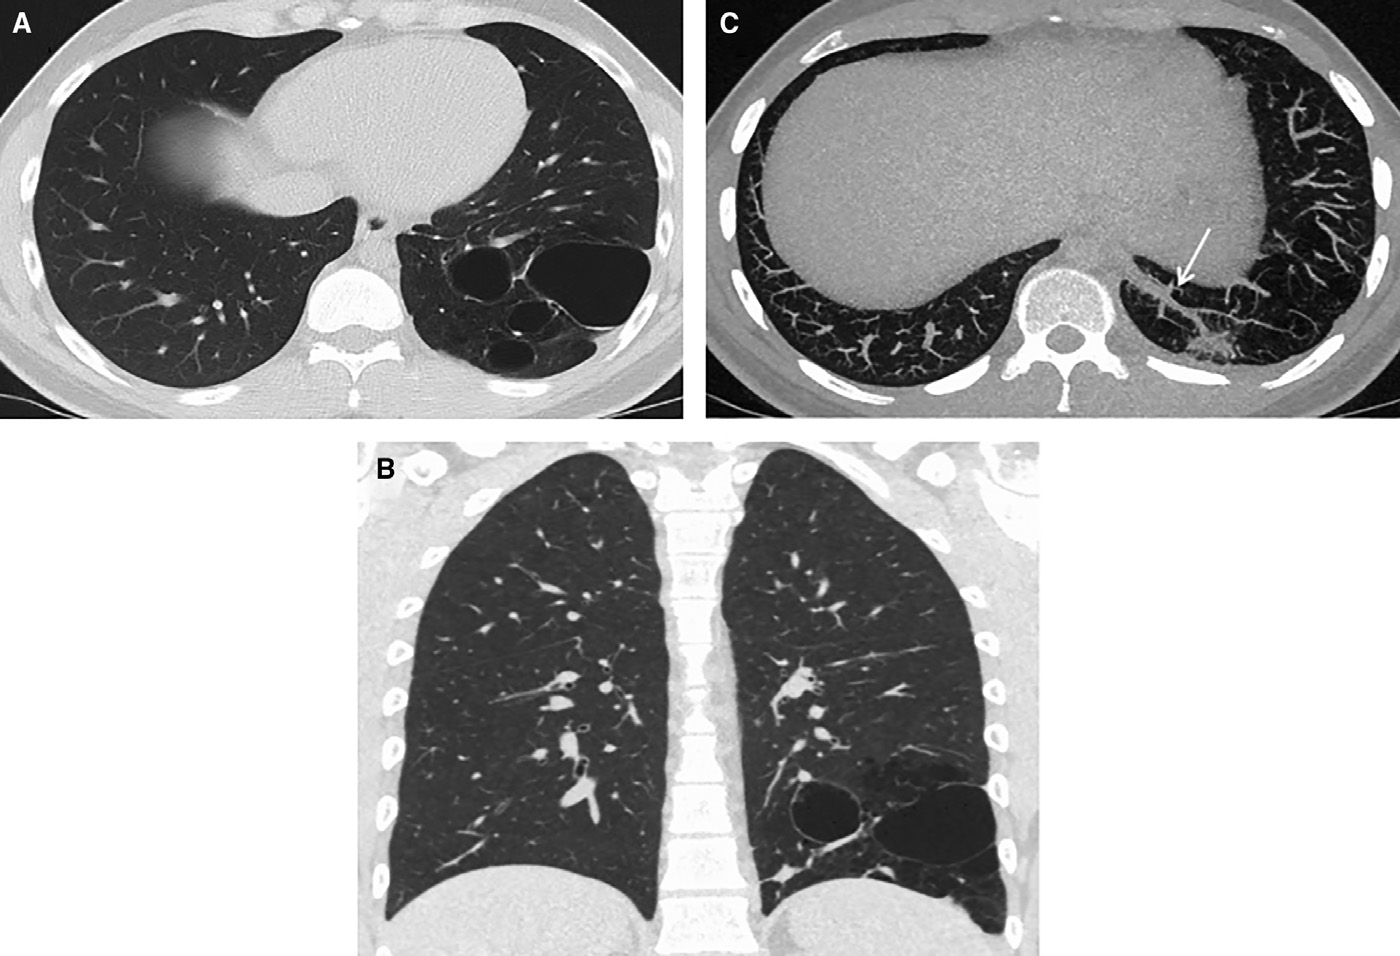

隨訪CT成像顯示左肺下葉基底段存在薄壁和多囊性病變,膈下主動脈供血異常(圖4)。多學(xué)科團隊討論后建議行左肺下葉切除術(shù),患者表示接受。切除組織病理學(xué)檢查發(fā)現(xiàn)囊狀擴張的氣腔,細(xì)支氣管內(nèi)襯纖毛上皮;無肉芽腫,未見惡性腫瘤證據(jù)(圖5A–5 C)。組織學(xué)表現(xiàn)與1型CPAM一致。鑒于影像學(xué)顯示動脈供血異常,患者被診斷為CPAM/BPS混合型病變。

圖4 (A)軸位CT圖像顯示累及左下葉基底部的薄壁、多囊性異常。(B)囊性異常的冠狀位圖像。(C)降主動脈的血供異常(實心箭頭)。